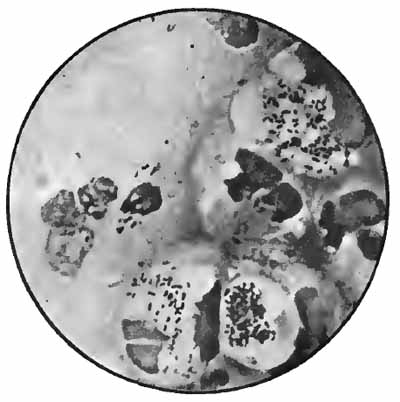

The more important structures to be seen in unstained sputum are: elastic fibers, Curschmann's spirals, [p. 27] Charcot-Leyden crystals, fibrinous casts, the ray fungus of actinomycosis, and molds. Pigmented cells, especially the so-called "heart-failure cells" (p. 43), are also best studied without staining (Plate II, Fig. 1).

Sputum from a case of actinomycosis

FIG. 8.—Sputum from a case of actinomycosis; stained (Jakob).

5. Actinomyces Bovis (Ray-fungus).—In the sputum of pulmonary actinomycosis and in the pus from actinomycotic lesions elsewhere small, yellowish, "sulphur" granules can be detected with the unaided eye. The fungus can be seen by crushing one of these granules between slide and cover, and examining with a low power. It consists of a network of threads having a more or less radial arrangement, those at the periphery presenting club-shaped extremities (Fig. 8). This organism, also called Streptothrix actinomyces, apparently stands midway between the bacteria and the molds. It stains by Gram's method.

[p. 32] Actinomycosis of the lung is rare. The clinical picture is that of tuberculosis.